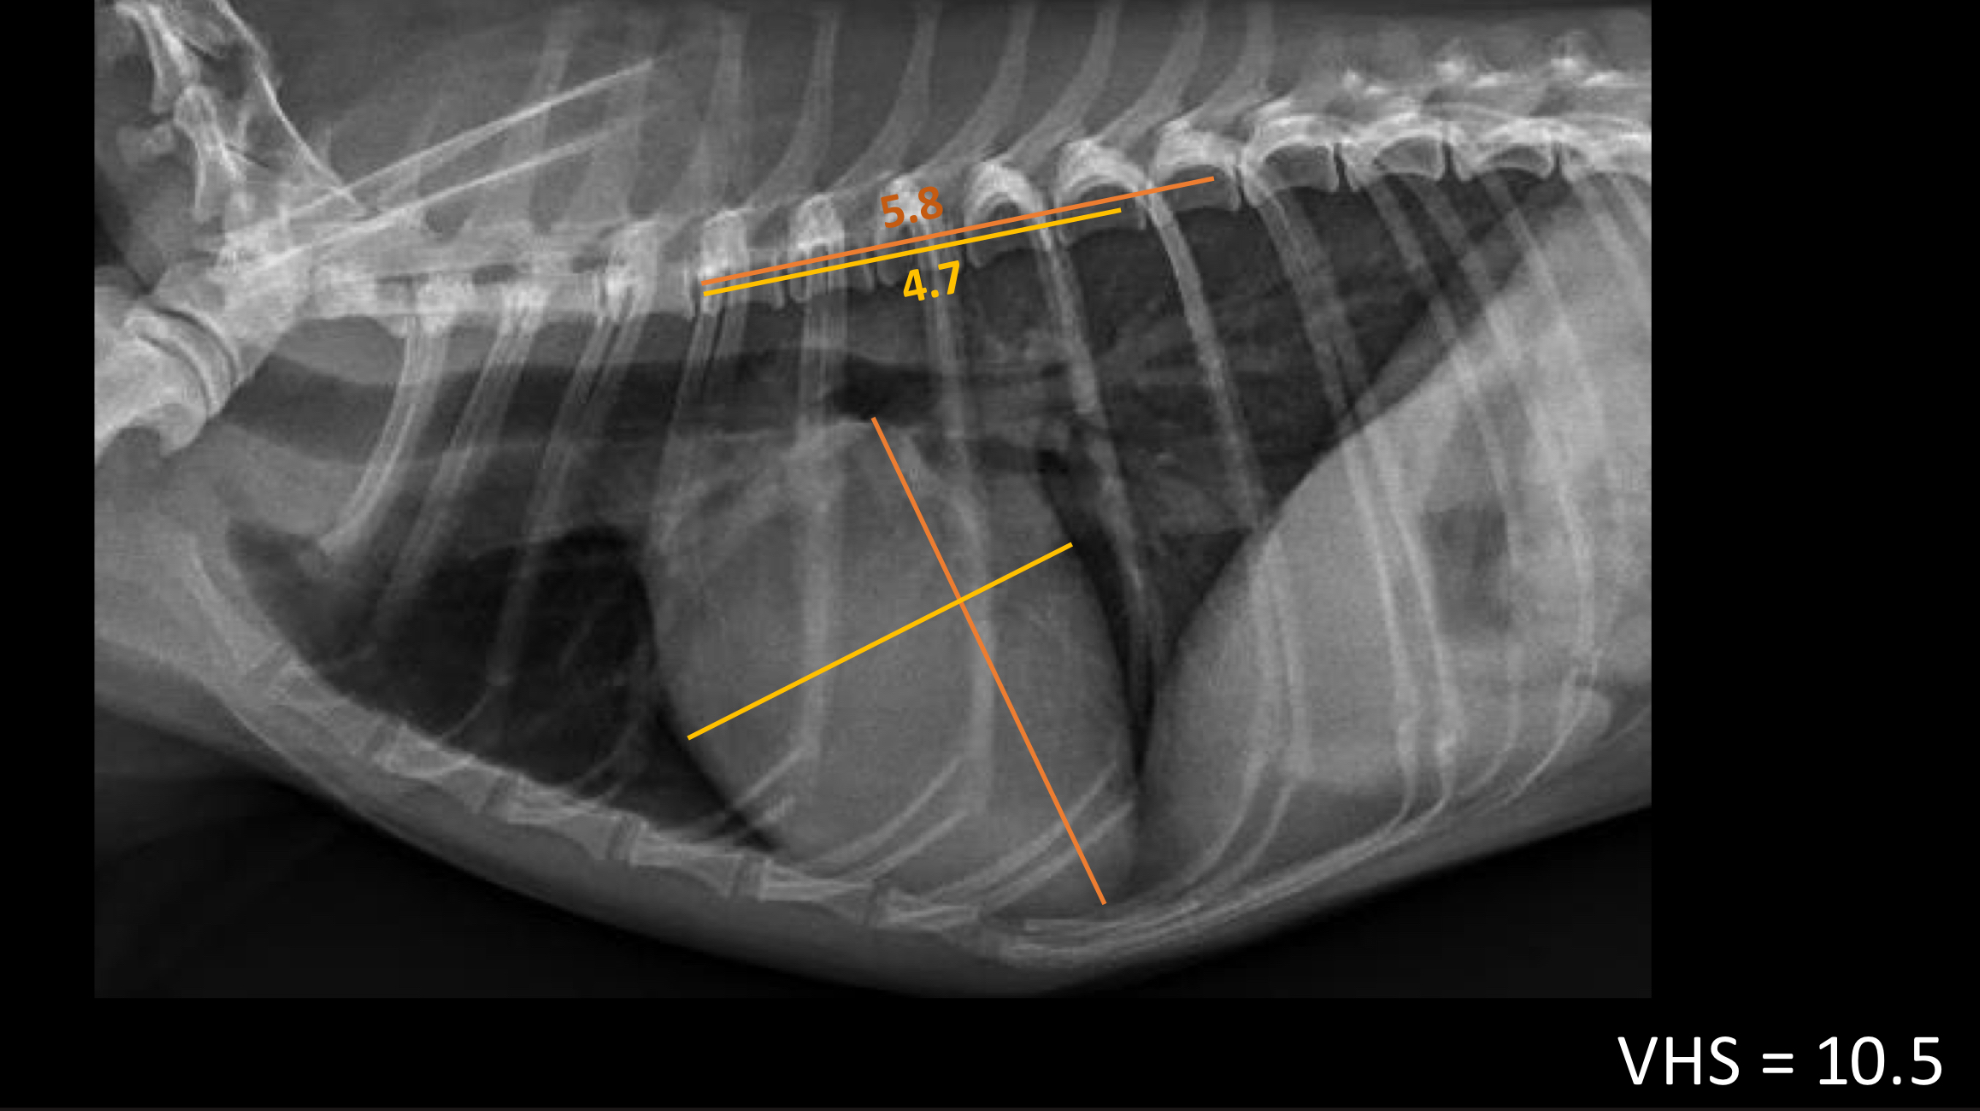

vertebra heart sum in dogs should be <_____ vertebrae

10.5 (measure width and height and add them together)

what is the next step for a dog with a VHS <10.5?

no treatment, repeat rads in 3-6 months

what is the next step for a dog with a VHS >10.5?

echocardiography